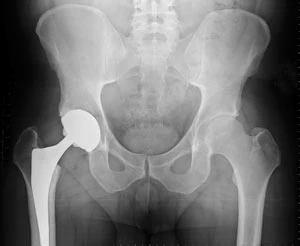

The use of biocompatible materials and coatings over the past 60 years is well documented for a range of different applications. For example, metals such as stainless steel and cobalt alloys have been widely used for orthopedic implants in joint prostheses applications because of their mechanical behaviors, including elastic modulus, wear and fatigue.

Orthopedic implant devices are likely to have undergone some surface coating or modification to reduce the effects of corrosion on the body - for example, render them biocompatible - or to reduce the potential of mechanical failure.